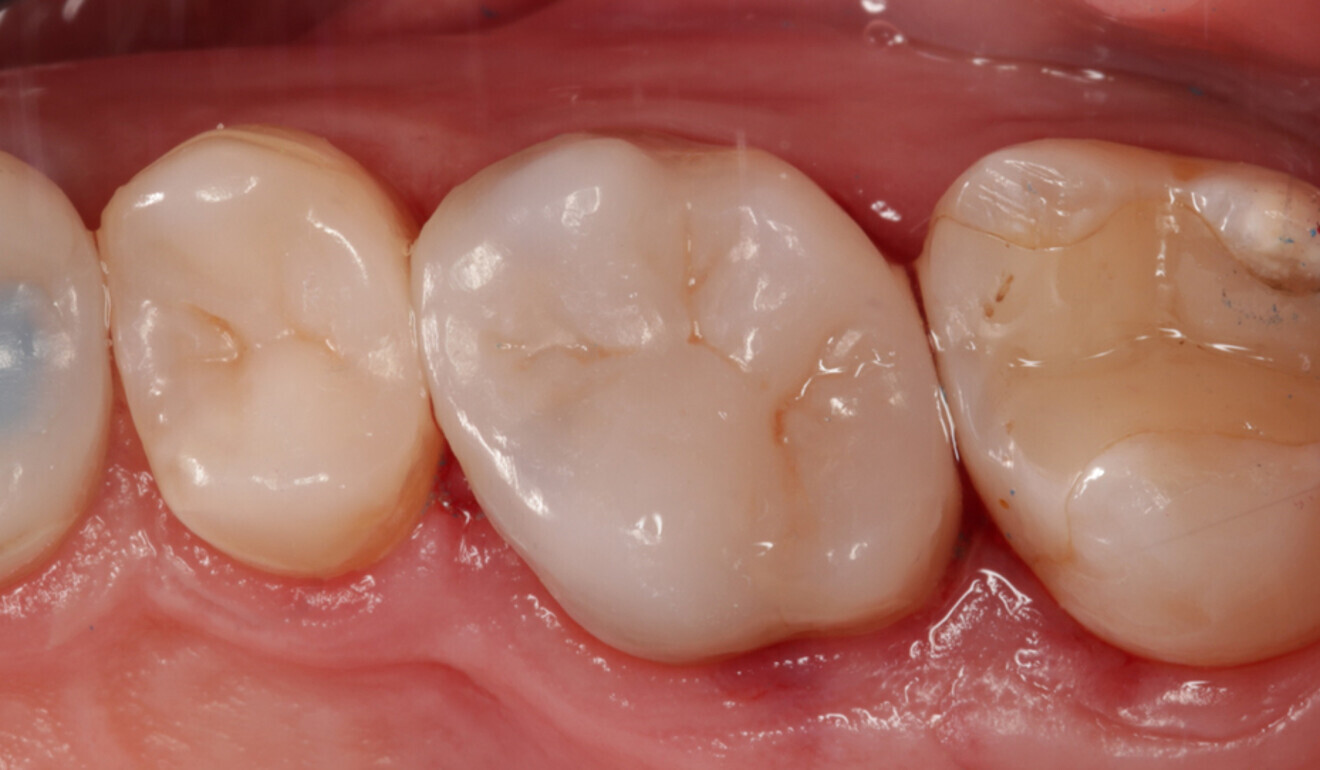

Fig. 20: Final effect after polishing with TWIST DIA for Composite. (Image: Kuraray Noritake Dental)